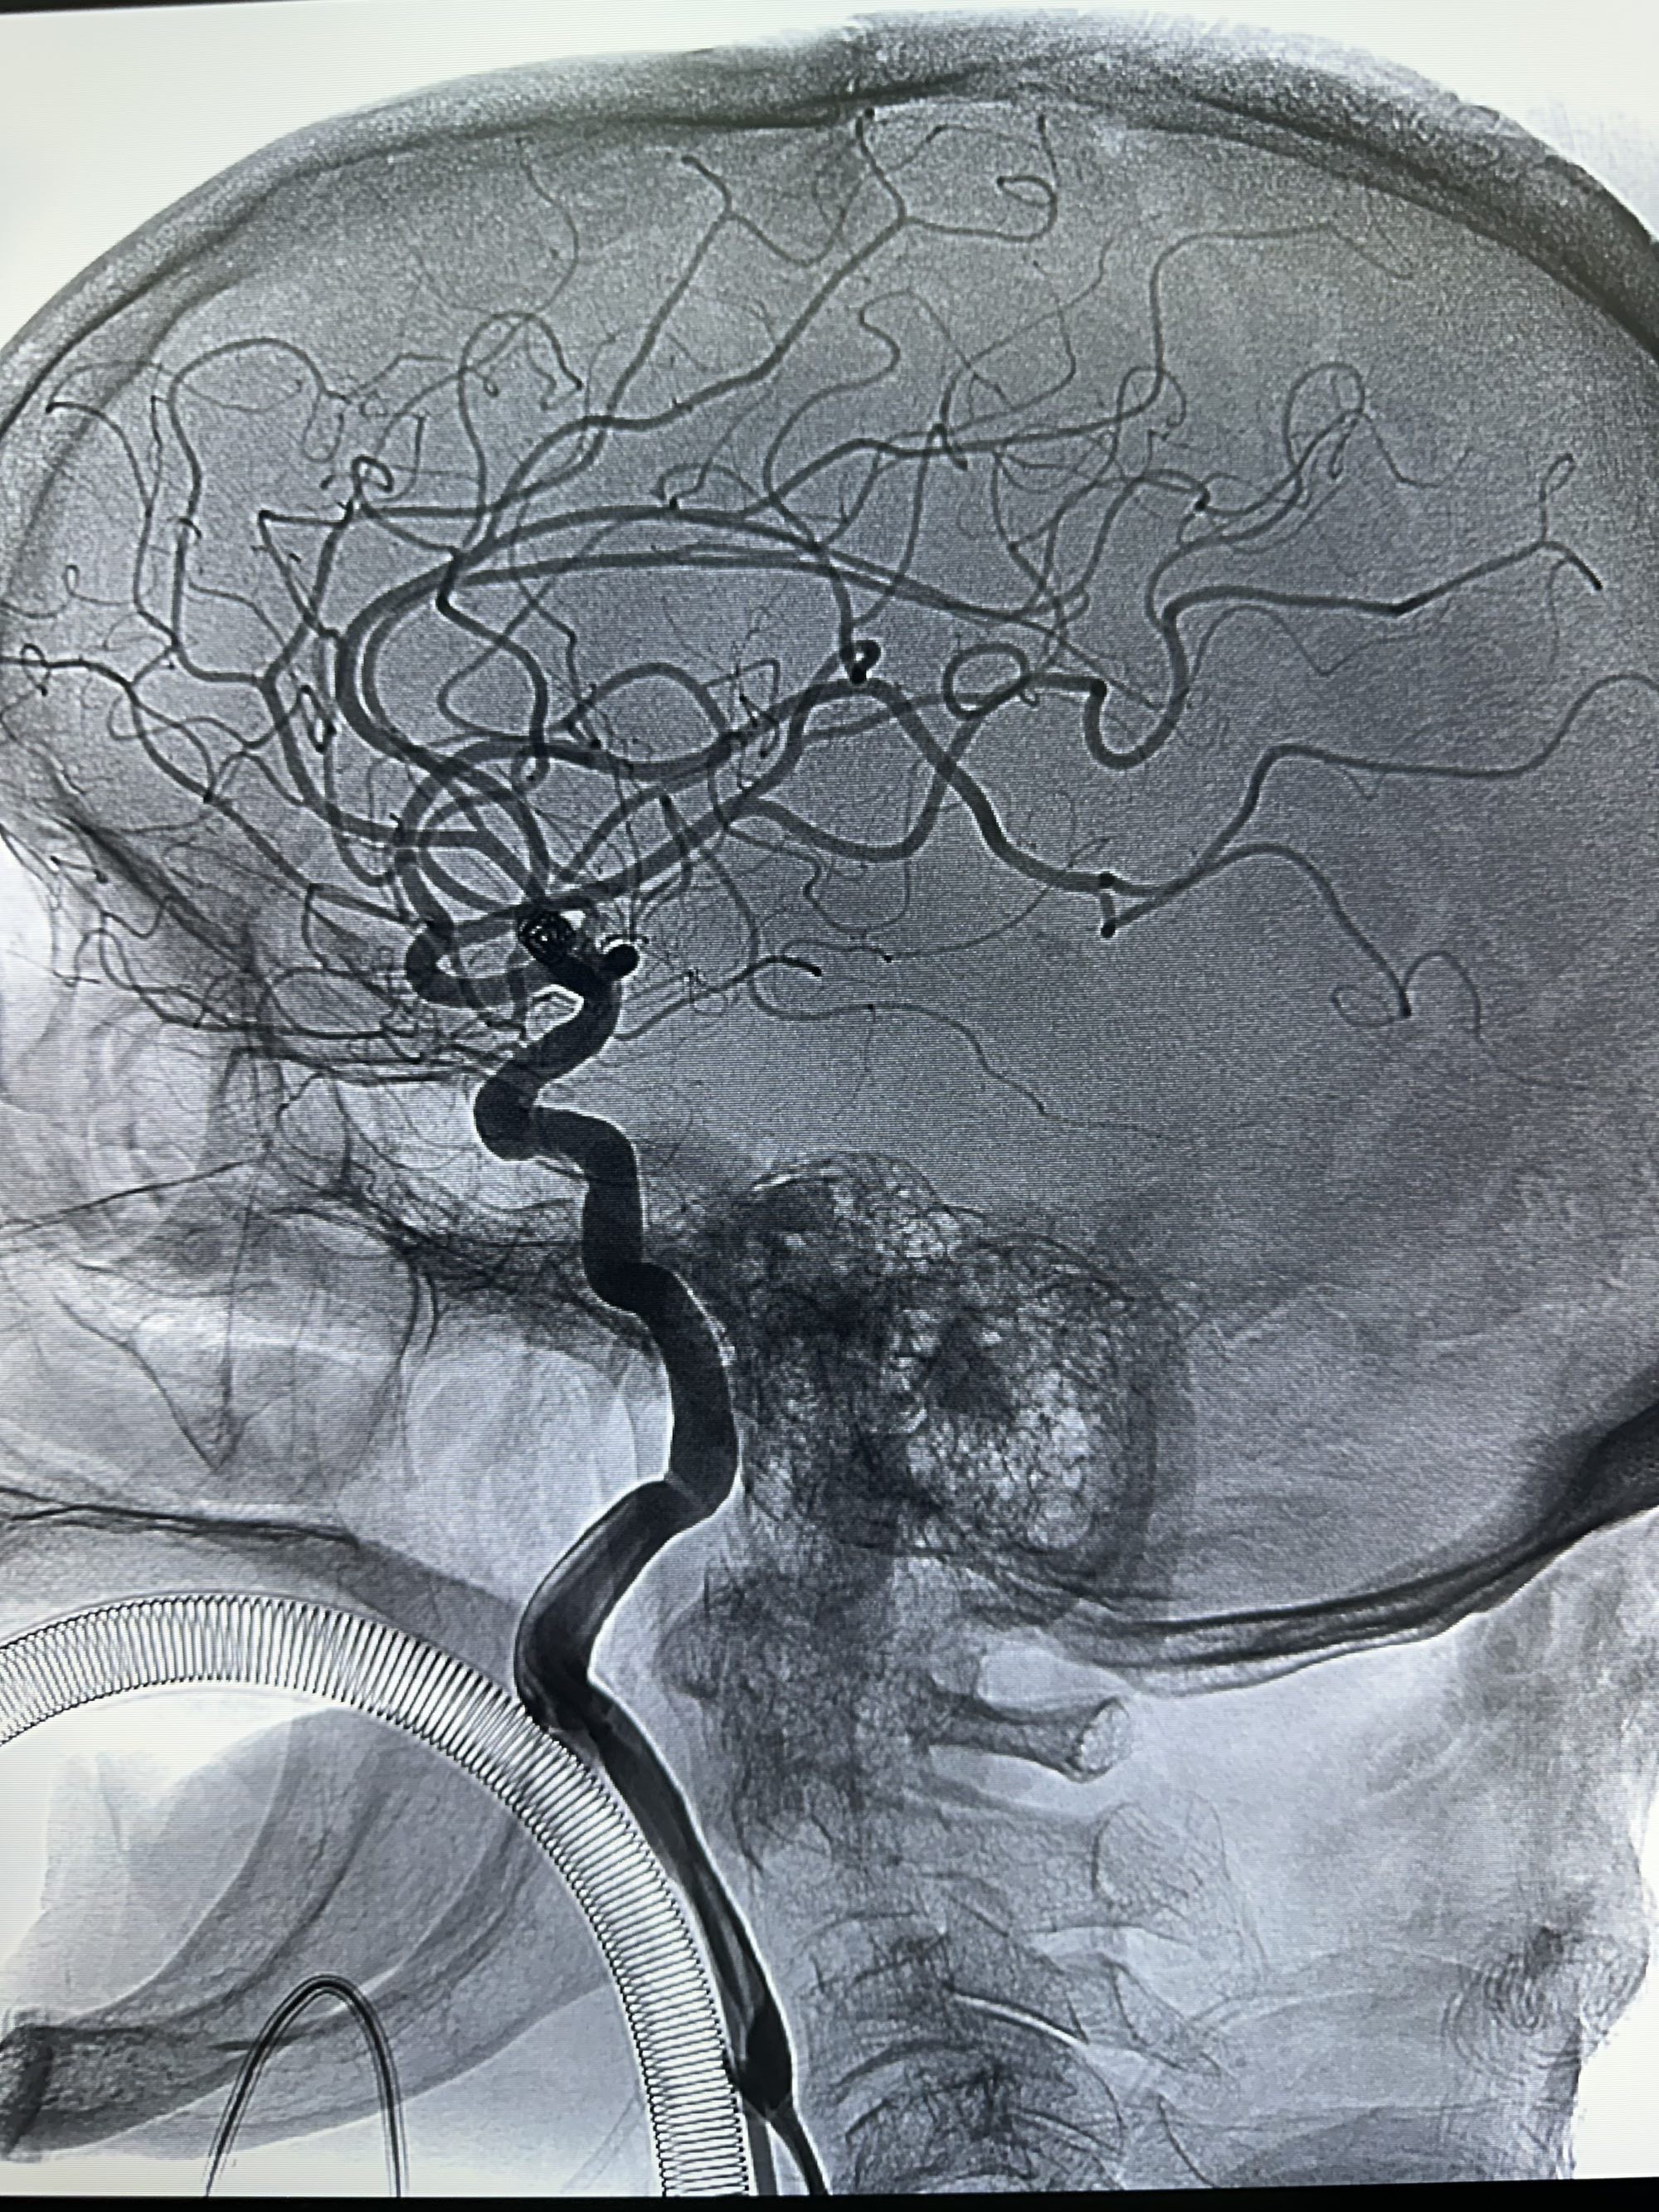

侧位

右侧颈内动脉造影